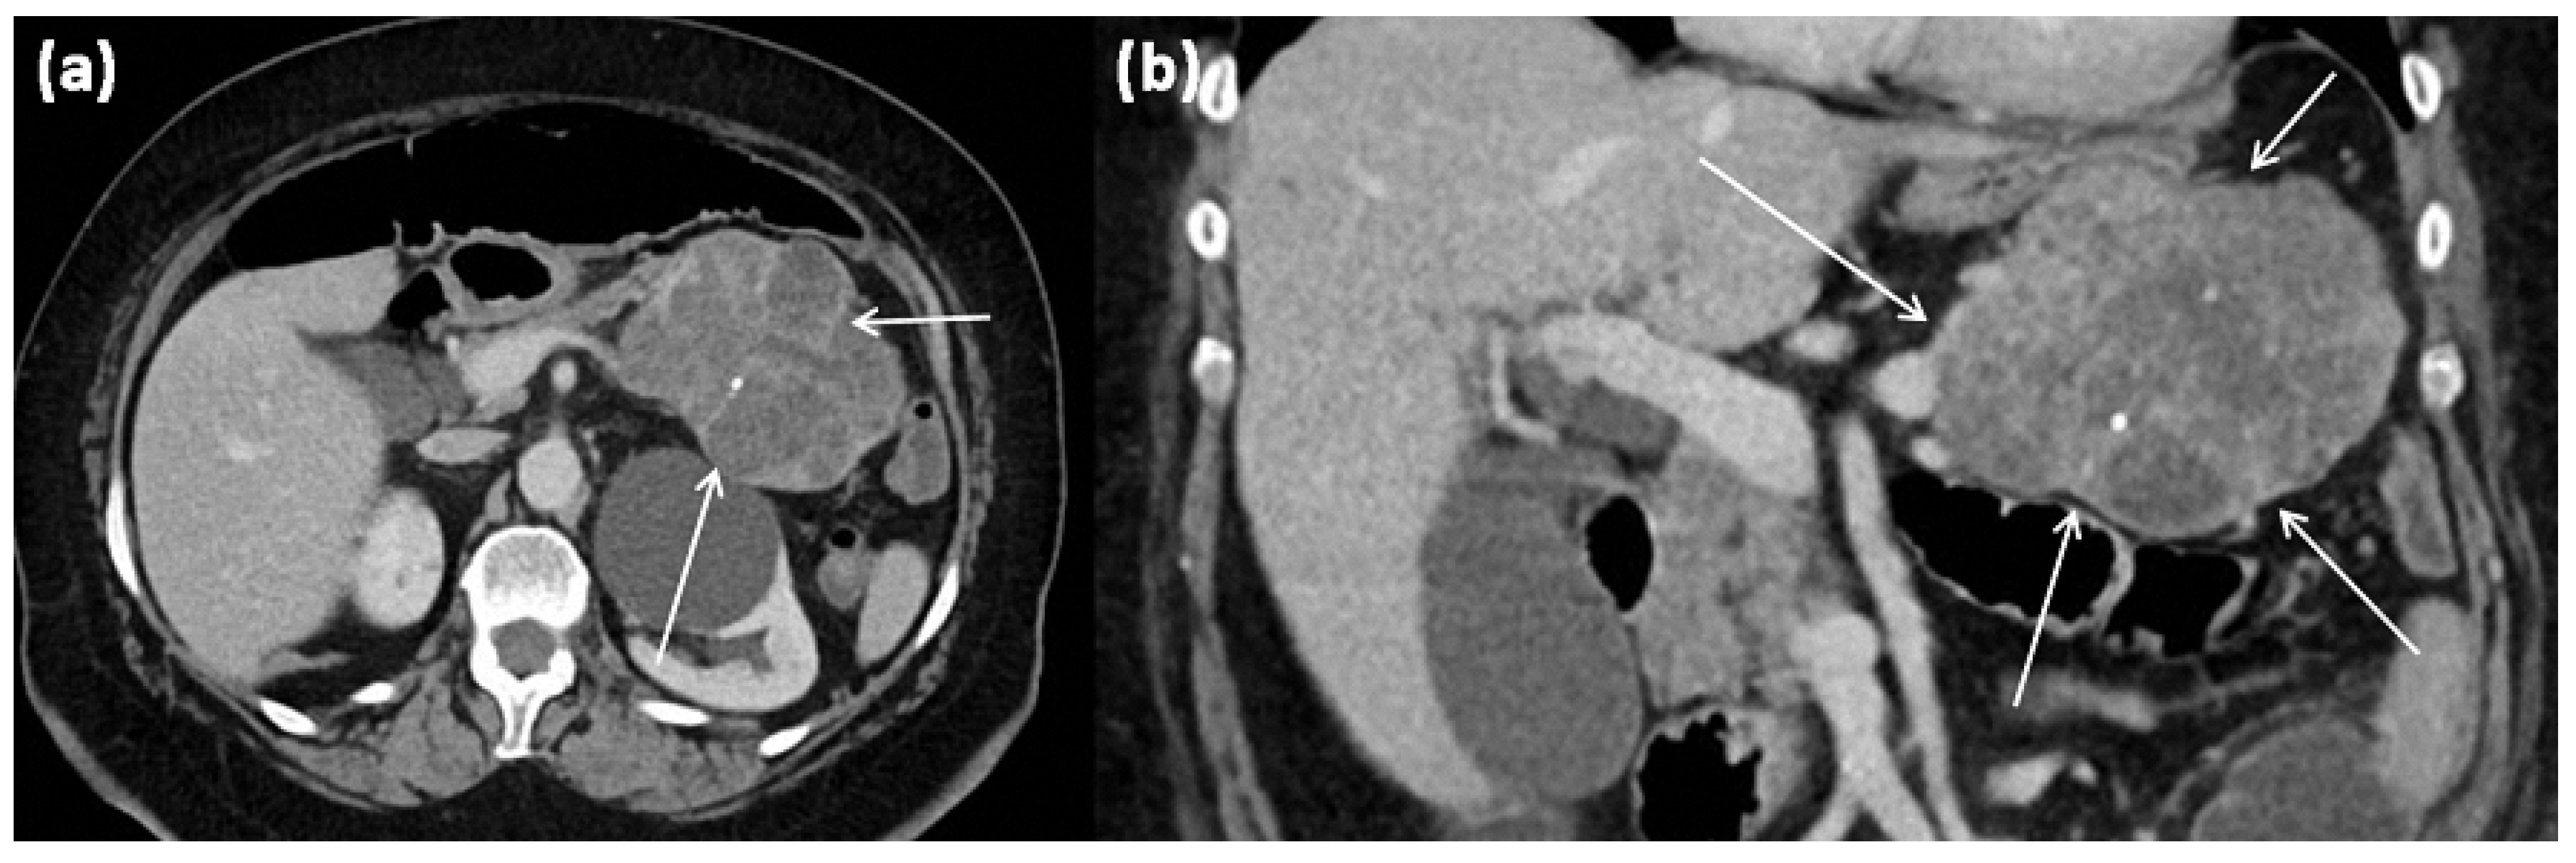

Figure 7.

CT of a 63-year-old female patient (portal venous phase) in axial (a) and coronal (b) view. CT shows a large polylobulated tumor of the pancreas tail with partly cystic parts (arrows). In addition, single punctate calcifications and sharp demarcation to surrounding tissue can be seen.

The most common type of SCN is serous microcystic adenoma (SCA). It is a relatively large (up to 25 cm, usually 6–11 cm), solitary, well-circumscribed tumor (Figure 7). It predominantly occurs in the body and tail. SCA presents a typical picture of honeycomb-like, arranged microcysts up to 2 cm, which are separated by delicate septa and do not communicate []. In the center of the lesion, a star-shaped scar is often found, which may show calcifications. This is presumably the fibrosed walls of a centrally located, collapsed cyst. The cysts appear fluid isointense, and the septa may show discrete contrast enhancement. The SCA appears most likely to arise from centroacinar cells. Immunohistochemically, the cells are positive for α-inhibin and for MUC1 and MUC6 (Figure 8). Women of older age are most frequently affected.